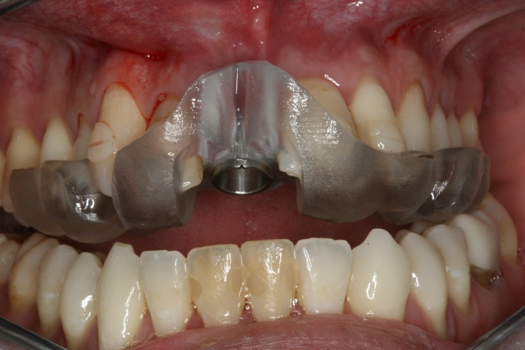

The next case follows the digital protocol for fully guided surgery and prosthetics. A CBCT radiograph, digital impression, and digital photography were the cornerstones to the success of this case. The 3D data set was electronically delivered to the dental laboratory. The data were merged and the process to develop the plan was initiated. The use of CBCT was essential in this case, particularly due to minimal space for placement of individual implants and single-unit crowns. The patient's chief concern was that she wanted to have single-unit crowns instead of fixed crown-and-bridge restorations because she was worried that she would someday find herself in an assisted-living facility; if that were to happen, she wondered, who would help floss under her bridge work? Her decision was to have single implants with individual crowns. CBCT technology is much more accurate in evaluating space maintenance and management.10 Periapicals in the past were rather close for calculating spacing; however, the CBCT identifies the buccal-lingual dimensions as well as the mesial-distal measurements. On review of the completed proposals for implant placement and provisionals, it was determined that there was sufficient spacing for implant placement to allow appropriate emergence profiles for the provisionals and then eventually the final single-unit cemented crowns. The proposal was accepted, and a 3D-printed surgical stent was fabricated, along with the PMMA provisionals (Figure 29 through Figure 35).

Fig 36. Anterior central view.

Figure 36

Fig 41. Abutment preparation.

Figure 41